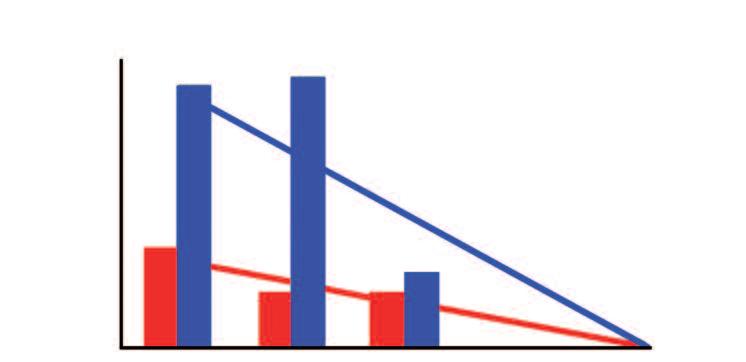

La ‘terapia’ convenzionale contro il cancro con il suo effetto deleterio per tutte le cellule sarà sostituita dal moderno metodo di 'regolazione cellulare'

Gli approcci terapeutici dominanti per questa malattia da parte della medicina convenzionale (la chemioterapia e la radioterapia) sono basati sul danneggiamento e sull'uccisione indiscriminata di miliardi di cellule del corpo nella speranza di eliminare il cancro.

Le statistiche dimostrano come questo approccio di ‘intossicazione’ sia un fallimento. Per molti tipi di cancro, la chemioterapia e la radioterapia non presentano alcun vantaggio, per altri tipi di tumore gli effetti sono stati minimi, a breve termine, e sono stati ottenuti attraverso sofferenze e un drastico calo della qualità della vita del paziente.

Quindi, esiste un oggettivo bisogno di una metodologia completamente nuova nella terapia del cancro. Questo nuovo metodo deve essere basato su una nuova comprensione della regolazione naturale delle cellule tumorali. Il fattore chiave per il controllo efficace del cancro è rappresentato da determinate sostanze nutritive. Esse sono in grado di correggere il malfunzionamento del software biologico delle cellule tumorali, senza intaccare il metabolismo delle cellule sane. Con questi presupposti scientifici, il termine cancro non evocherà più il sentimento di paura che è solito accompagnare questo tipo di diagnosi.

Chemioterapia

Radiazioni

Regolazione naturale implica

• Inibizione della crescita tumorale

• Inibizione delle crescita delle metastasi

• Incapsulamento dei tumori

• Eliminazione selettiva delle cellule tumorali

Il fattore chiave della vittoria sul cancro: Regolazione invece di intossicazione